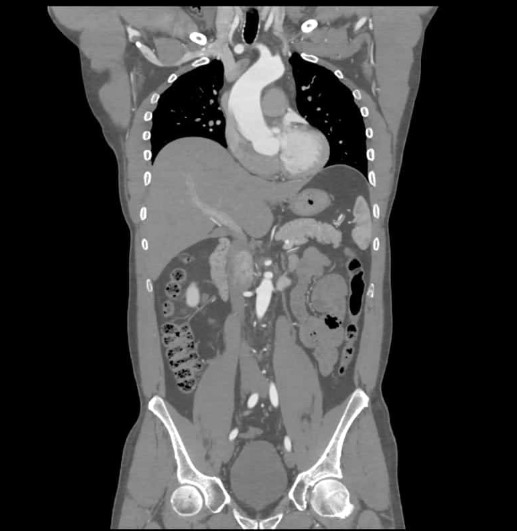

Abd CT scan